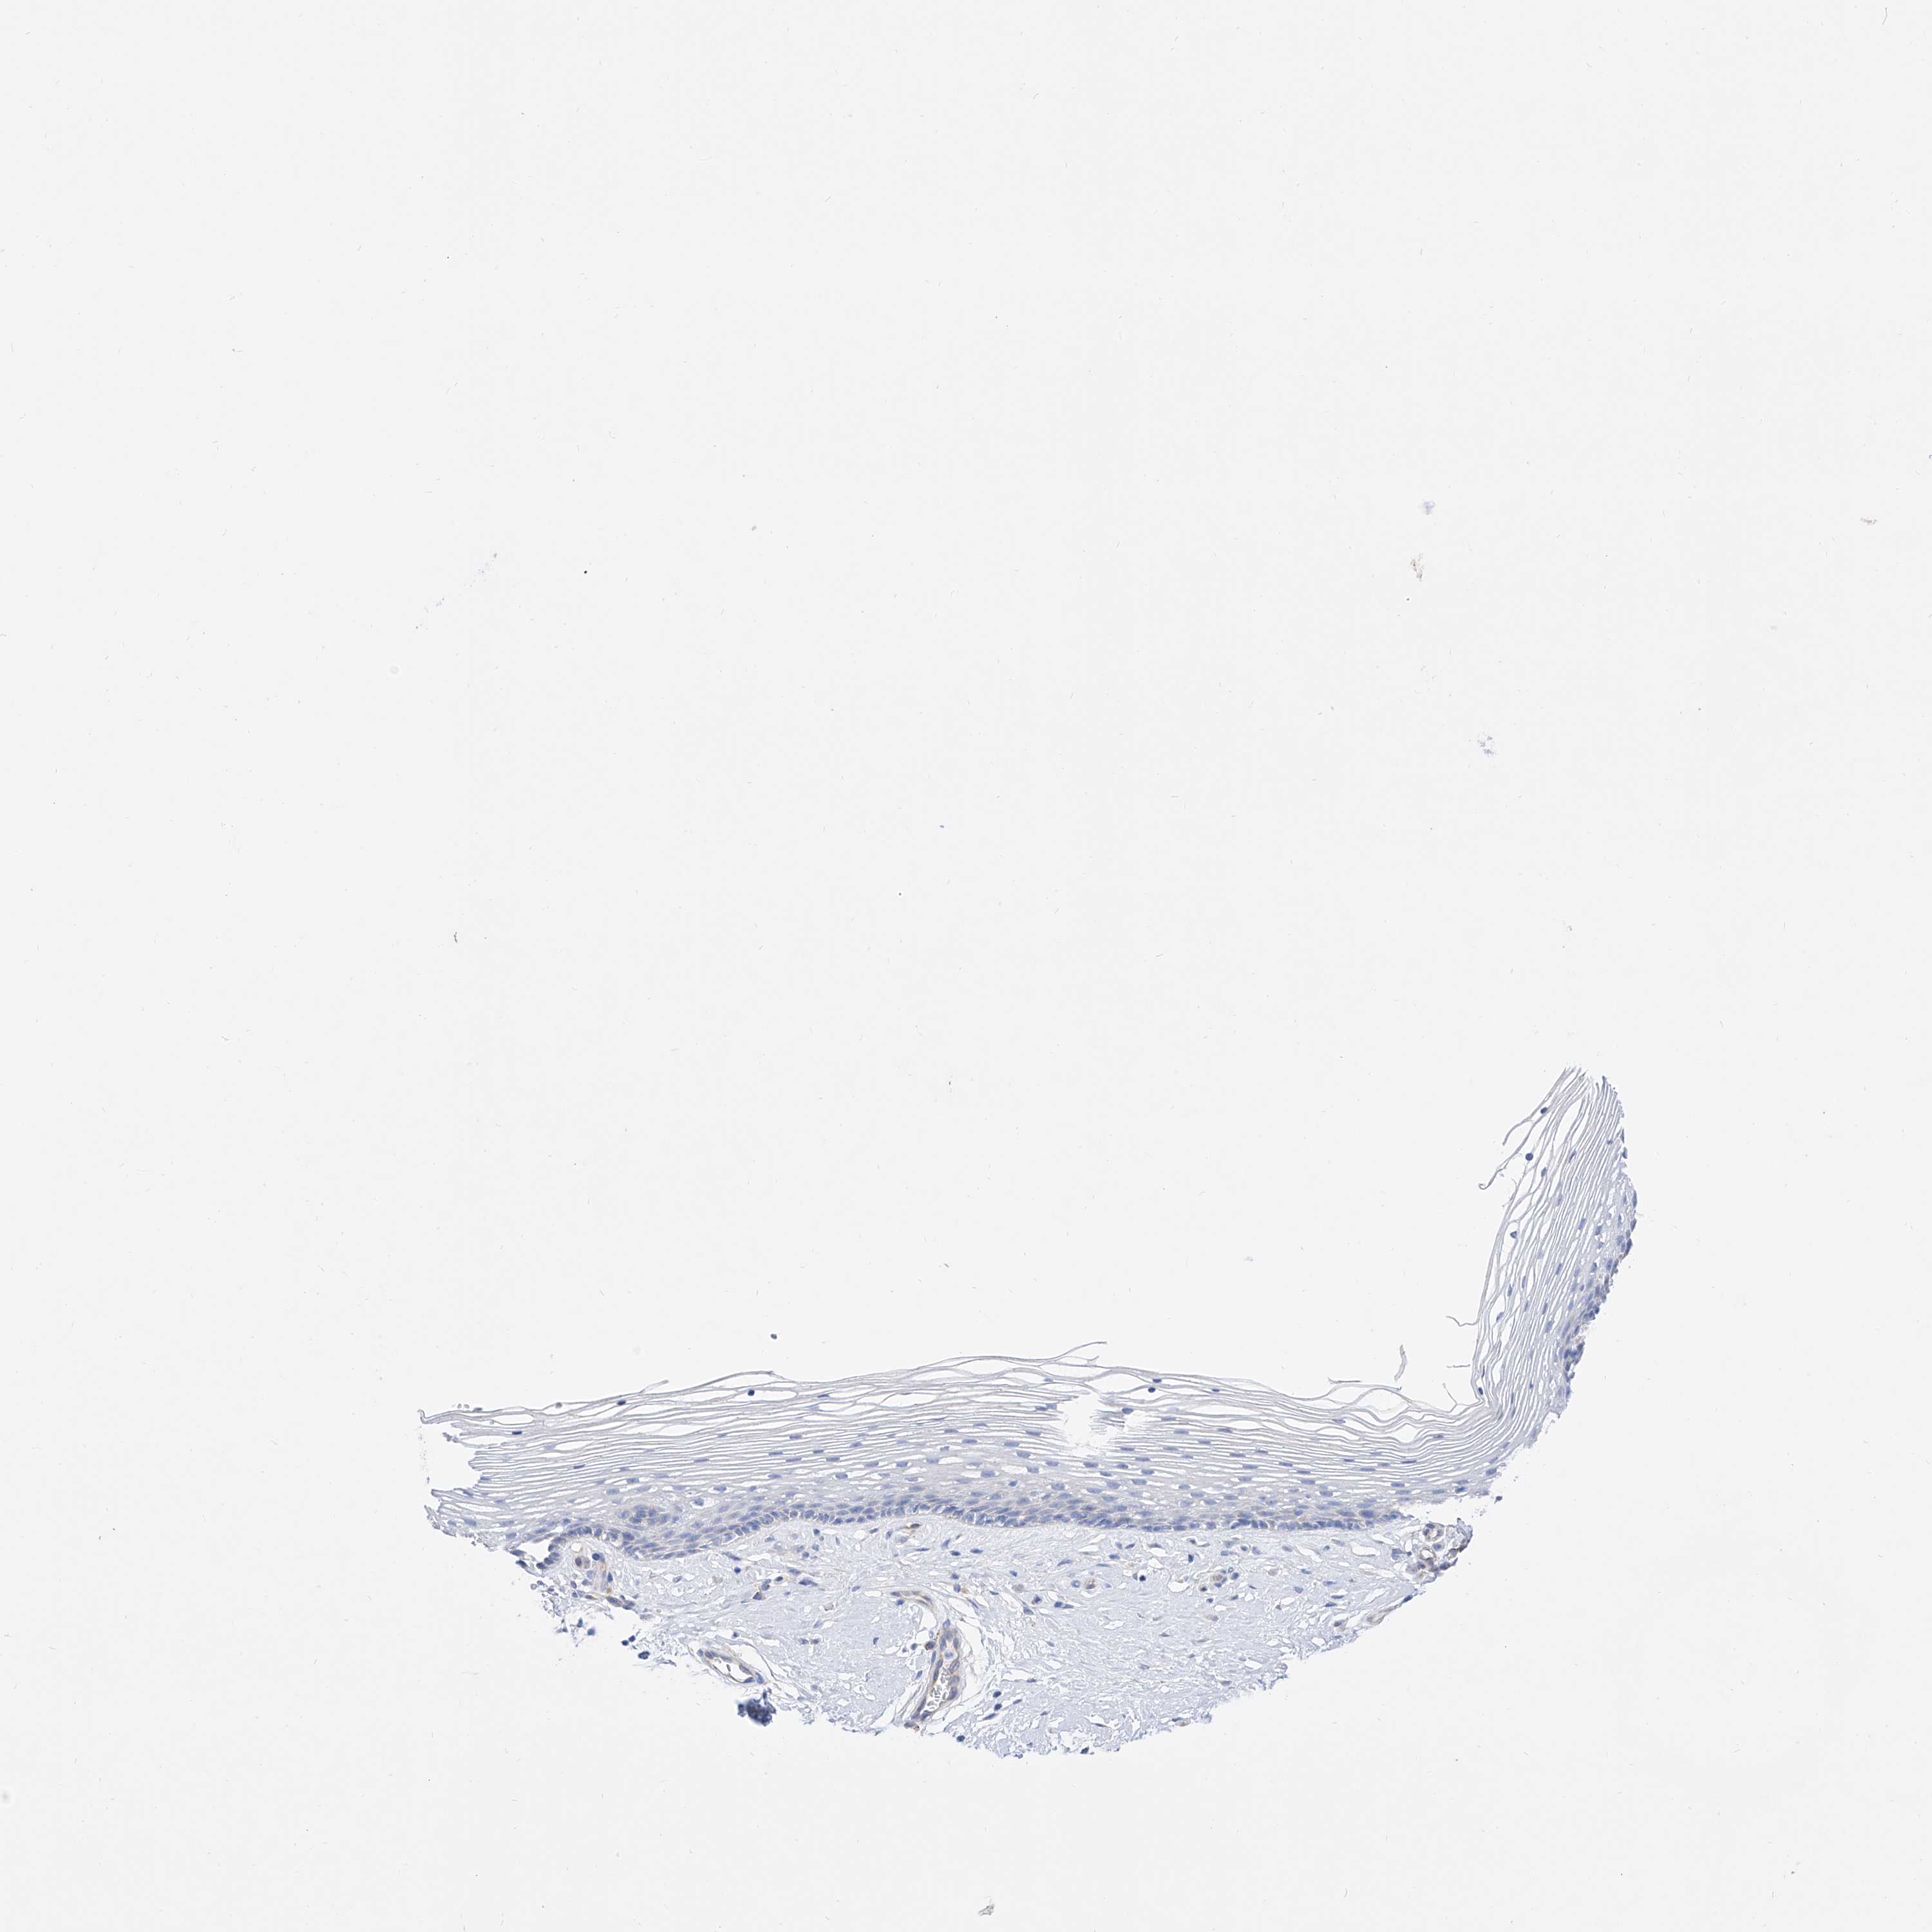

VAGINA - Antibody stainingi

Antibody staining in the annotated cell types in the current human tissue is reported as not detected, low, medium, or high, based on conventional immunohistochemistry profiling in selected tissues. This score is based on the combination of the staining intensity and fraction of stained cells.

Each image is clickable and will lead to virtual microscopy that enables deeper exploration of all samples and also displays staining intensity scores, fraction scores and subcellular localization as well as patient and tissue information for each sample.

Antibody HPA023631Antibody HPA023635

Squamous epithelial cells HighNot detected